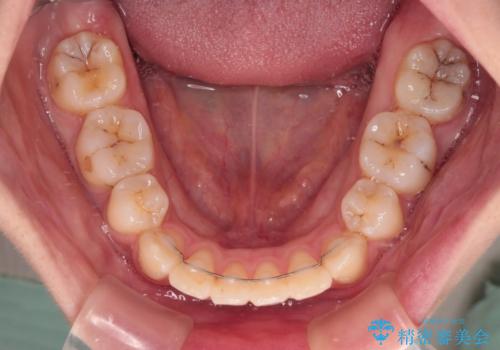

- 前歯のデコボコや口元の突出感、口の閉じにくさを気にして来院された患者様です。

上下左右第一小臼歯4本を抜歯し、ワイヤー装置にてデコボコを解消しながら口元を引っ込めるよう矯正治療を行うこととしました。

抜歯スペースを閉じている過程で、左側の上下犬歯が引っかかってしまい、進捗が停滞しましたが、当初予定の2年~2年半の間で無事に治療を終えることができました。